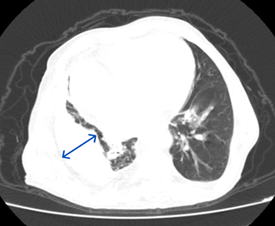

The duration of his anti-tuberculosis treatment and the specific medications he got remain unknown. He has a smoking history of 20 packs per year, has been smoke-free for 35 years, and abstains from alcohol consumption. He had hypertension and heart failure, but the patient had no history of regular drug use. He has been having frequent coughs, phlegm and shortness of breath for about 20 years. He was given oral antibiotic treatments, but when his complaints started to regress, he did not go for follow-up examinations. He used oral antibiotics 4 times in the last year, and hospitalization was recommended once, but the patient did not accept it. Looking at the patient's retrospective examinations, pleural thickening, areas containing fluid density, and calcifications were observed in the right hemithorax in the Thorax CT scans taken in 2010 and 2022 (Figures 1 & 2). In the CT scan of the patient taken in January 2024, approximately 3,5 cm was observed on the right hemithorax, which could be evaluated in favor of pleurisy sequelae (Figures 3 & 4). Sputum analysis for three Acid-resistant bacilli tests was negative. There is no elevated sedimentation, CRP, or leukocytosis.

Figure 3 Mediastinal window of January 2024 thorax CT, the lesion remained stable and no fistula developed during the 14-year period. Comparative evaluation with previous images is very valuable in the diagnosis process.